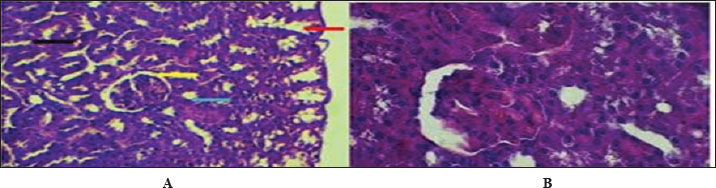

Figure 6 shows that the maturation of kidney tissue was visible on the later low-power H&E section of the 2-week-old hamster kidney compared with the 1-week specimen. The red arrow indicates how the renal cortex parenchyma is arranged, and the tubular regions are increasingly gathered and distinguished. Because the glomerulus was better developed, there was a clearer and bigger outline of the renal corpuscle. The yellow arrow marks the tubules that have been collected, and they now have distinct profiles and clear lines between epithelial cells, showing that urine concentration is starting and nephron structures are also dividing further. Figure 7 (Section Masson) implies that the capsule of the kidney cortex has received more fibrous support than in the previous stages. Columnar epithelial cells (marked by the blue arrow) were longer and better arranged in the inner part of the sac than they had been a week ago. The red or pink epithelial layer and the cytoplasmic structure were clearer from the blue collagen, indicating the formation of different tissue compartments in the body. Figure 8 presents the appearance of a hamster’s ureter at 2 weeks, stained with H&E in Figure A and with Alcian blue in Figure B at both 10x and 20x magnification. The lumen (red arrow) was slender and surrounded by a better-defined epithelial lining in both images. Simple squamous epithelial cells are marked by the yellow arrow in the transitional epithelium, and the blue arrow indicates a smooth muscle layer below. Mucosubstances in the epithelial layer became more noticeable in panel B because the Alcian blue stain was used, suggesting more mucus secretion for passing urine and shielding the bladder wall. Figure 9 includes two histological images of the renal cortex of a 3-week-old hamster. One was stained with hematoxylin and eosin (A) and the other with Masson’s trichrome (B) under 40x magnification. There was an increased formation of renal corpuscles in every area, where the capillary tufts were evident (yellow arrows). The red-marked proximal tubules have a well-formed brush border, and their cytoplasm is colored eosinophilic. Both images have blue arrows that confirm that the renal veins were connected with the blood vessels in the cortex. In Fig. 10, Panels A and B, Masson’s Trichrome (A) and Van Gieson (B) stains were used for transverse sections seen at 20x. The red arrows show where the unambiguous ureteral lumen was located. Simple squamous epithelium was highlighted by yellow arrows and stratified. The blue arrows denote the muscles found in the area, whereas the black arrow in panel B marks the pink layer seen on the outside called the serosa. Currently, the ureter looks complete, as confirmed by its multilayered structure, and is ready. Fig. 11 shows the renal cortex from a 2-month-old hamster stained with PAS (A, 20x) and H&E (B, 40x). Panel A shows that the renal capsule is organized and composed of fibrous tissue. The yellow arrow indicates that the advanced renal corpuscle has a distinct Bowman’s space, and the blue arrow indicates a major proximal tubule marked by its brush border and PAS-positive basement membrane. The black arrow indicates the wider lumen and the pale cytoplasm of the distal tubule. In the H&E image, the two main kinds of tubules were easily identified, proving that the nephron has developed completely and matured in the cortex. At a magnification of 40x, the renal corpuscle is clearly seen in Masson’s Trichrome (A) and Van Gieson (B) stained slides, as shown in Fig. 12. The blue arrows show complete glomerular capillaries that were properly perfused and assigned a consolidated mesangial matrix. These arrows were aimed at the juxtaglomerular cells on the vascular side, indicating that they were ready to release renin. The red arrows show the urinary pole and the proximal tubule entrance, indicating that the nephron was intact. The black arrows indicate sections of the tubules that lie far from the glomerulus. They also highlight how the nephron is made up of important sections and how the corpuscle becomes an effective filtration unit. Fig. 13 shows a sliced ureter in a 2-month-old hamster demonstrating that its structure was fully mature by Masson’s Trichrome (A) and Van Gieson (B) staining. The red arrows show a wideness to the ureter, proving that the epithelial and muscular layers have healed well. The yellow arrows point to a fully developed urothelium and show simple squamous to cuboidal features according to the ureter location. The thicker and more organized circular muscle groups were observed, where the blue arrows were found inside the walls.

Fig. 11. Cross-histological section of the renal cortex in hamsters aged 2 months, consisting of the capsule (red arrow), distinct renal corpuscles (yellow arrow), and proximal tubule (blue arrow) and distal tubule (black arrow). A- 20x. PAS stain. B- 40x. H&E.

Fig. 12. Cross-histopathological section of renal corpuscle in hamsters (2 months old) consisting of glomerular capillaries (blue arrow) and juxtaglomerular cells with urinary pole distal tubule (A- 40x. masons stain, B- 40x. Van Gieson stain).

Fig. 13. Cross-histological section of the ureter in hamsters aged 2 months showing a deep lumen (red arrow) in the middle, a simple squamous epithelial layer (yellow arrow), and smooth muscle (blue arrow), A- 10x. Masson’s trichrome stain, B- 40x. Van Gieson staining.

At 1 week of age, the kidney of the hamster showed typical signs of early postnatal development, such as a defined renal capsule, not so mature renal corpuscles with narrow spaces where blood fluid was processed, and the inner tubule walls were mainly made up of simple cuboidal cells. These results showed that in rodents, development of the kidney glomerular and tubular structure continues shortly after birth, serving the kidney’s maturation (Kose et al., 2020). Indeed, the thin connective capsule seen on both H&E and Masson’s Trichrome stain indicates that mesenchymal cells are already dense, and this observation fits with what has been found in developing rodent species, where the renal capsule becomes thicker and starts changing by the second week after birth (Singh et al., 2022). A hamster kidney has renal corpuscles with a narrow space for forming urine, and the Bowman’s capsule is less developed, indicating that glomerular growth in the hamster has just begun. These observations are consistent with previous findings on neonatal rats and mice that the kidneys’ filtration ability was limited during the first week of life (Lee et al., 2019). Observing articular arteries near the glomeruli is essential because it represents vascular recruitment that supports the continuous creation of blood vessels in the developing kidney tissue (Chou et al., 2021). In addition, Alcian blue staining confirmed the presence of acidic glycosaminoglycans in the basement membranes, which is an important early indicator of nephron development and the formation of tubule centers in epithelial cells (Sajjad et al., 2020). The appearance of Henle’s loops and collecting ducts on slides with PAS and Van Gieson stains shows that urine was being concentrated at this point, albeit only to a small extent in the renal medulla. As Zhang et al. (2023) described in their study, the simple squamous epithelium found in the thin limbs of Henle’s loop in neonatal rodents was a sign that the structure was immature and unsuitable for effective countercurrent exchange until the third postnatal week. In addition, the PAS stain revealed cells that looked like zymogens, which might match immature tubular epithelial cells that were not yet fully differentiated (El-Mahdy et al., 2019). Postnatal growth and development in the ureter were observed after H&E, Alcian blue, PAS, and Masson’s trichrome staining. The fact that the lumen was narrow and surrounded by a simple squamous epithelium, along with the emergence of a double layer of smooth muscle tissue, suggests the initiation of peristalsis. In newborn rats, smooth muscle development occurs in the late fetal stage and continues after birth to form the two muscle layers (Matsumoto et al., 2020). At this point, Alcian blue detected in the ureter confirms the presence of mucopolysaccharides that could help protect the lumen and make the tract more flexible (Ishak et al., 2022). It could also show early formation of the stromal matrix in the capsule and interstitium by finding collagen fibers during Masson’s trichrome staining. It is essential to keep the structure of the kidneys intact and to attach the nephrons. Wu et al. (2021) revealed a similar behavior in the kidneys of newborns, as increased collagen types I and III are seen during the first postnatal week, and these help form tubules and stabilize blood vessels. At 1 week of age, the hamster kidney and ureter are changing from a prenatal structure to a fully functioning one. They confirm what has been found in mice and improve the development of the kidneys and ureters in hamsters, a major animal used in renal medical studies (Al-Rubaye et al., 2018; Kim et al., 2024). The 2-week observations revealed that both glomeruli and tubules were maturing and specializing in the kidney. The cortex appears thicker, has more cells, and the parenchyma is organized more clearly in these structures. Bowman’s capsules were thicker, and the renal corpuscles were also more formed. Important changes in the kidney, including elongation of podocyte foot processes and growth of glomerular capillaries, occur between days 10 and 15 after birth (Abdel-Rahman et al., 2020). The presence of PAS-positive material in the capsule and basement membranes of Bowman’s capsule is another indication of glycoprotein accumulation during postnatal kidney development. The renal corpuscles stand out with their unique build and know-how of filtering blood. A further examination in neonatal Wistar rats indicated that the parietal epithelial cells depositing more extracellular matrix material caused the thickening of the Bowman’s capsule during the second week postbirth (Salem et al., 2021). Zymogen-like cells in the proximal tubular epithelium might start the development of enzyme creation, as it was shown in rabbit and guinea pig kidneys when renal tubules are starting to differentiate (Zahra et al., 2019). The medullary region contains vertically arranged, straight tubules that are covered by simple columnar epithelium. They probably represent the early part of the collecting ducts and the thick parts of the ascending limbs. Setting up the renal structure in this manner was necessary to develop the main renal countercurrent system. These developments in medullary extensions and epithelium were in line with the explanations provided by Balasubramanian et al. (2018), who said that they boost both sodium reabsorption and urine concentration in rats beginning on day 14 after birth. In this process, the Van Gieson stain enables the maturation of the renal tissue and supports the correct placement and stability of nephrons. There were more layers in the renal capsule, indicating the readiness of the tissue to handle the increased blood pressure in the artery. In Syrian hamsters and tree shrews, the renal capsule thickens with fibroblasts and collagen I during early growth, acting as added protection from trauma (Nasr et al., 2023). The better organization of subcapsular nephrons indicates that nephrogenesis is very close to finishing—a stage usually completed at the end of the second week in most rodent models (Barakat et al., 2019). When viewed under Alcian blue staining, the transition zone of the ureter has several cell layers and exhibits heavy accumulation of mucus. The muscularis muscle layer develops into circular and longitudinal bundles to allow regular urine movements. A study on mouse postnatal ureter development found that muscle cells begin to contract with coordination once the tube’s layer and inner lining have been completed on Days 10–18 (Farag et al., 2022). The widening of the ureter’s lumen, which was observed in slices stained with hematoxylin and eosin and with PAS, also demonstrates the organ’s readiness for more renal urine. These results indicate that on postnatal day 14, there were significant changes in the glomerular, tubular, capsular, and ureteral structures of the kidney and ureter. As a result, these changes ensure that vital filtering, reabsorption, and elimination functions are available for self-control of the body, as backed up by studies of several rodents and ensuing histological and ultrastructural sessions (Al-Khafaji et al., 2020; Alshammari et al., 2023). When the Alcian blue stain was positive, mucopolysaccharides were still being produced for the protection of the urothelium, and when PAS staining was present, it indicated that the basement membrane had grown and differentiated properly. In hamsters, the kidneys show significant improvement at 3 weeks after birth as the renal corpuscles, proximal tubules, and blood vessels can be easily distinguished. Mature glomerular tufts and an increase in the size of Bowman’s spaces which was clearly observed by Masson’s trichrome dye staining. Similar to 17- to 21-day-old mice and Mongolian gerbils, this same order of development is typical for nephron maturity and glomerular capillaries in rats (Al-Dosari et al., 2021). Clear brush borders in the proximal convoluted tubules show that the kidneys have achieved a significant absorptive function, reflecting the situation in rodent models (Saleh et al., 2023). PAS-stained cortex reveals that the capsule and widespread tubules are clearly visible. This suggests that the blood vessels were being organized and the tubular alignment was increasing. In the striated distal segments, the PAS-positive reaction indicates that more basement membrane proteins were present, which enhanced ion movement and strengthened the tubules while reabsorption was going on (Okasha et al., 2022). Similar to previous research in gerbil and hamster models, the so-called regenerating zone shrinks around the third postnatal week, indicating that nephron growth is finished and the last maturation phase begins (Abbas et al., 2021). The glomerular structure was stained using Van Gieson stain to clearly separate the layers of Bowman’s capsule, visceral, and parietal. Evidence from previous studies was confirmed by the presence of red collagen in the capsular region, indicating that extracellular matrix deposits are important for stabilizing kidney growth after birth (El-Taher and Mahrous, 2020). In addition, the structure of the organized capillary beds and division of glomerular layers corresponds to the time when podocytes and endothelial cells were fully matured in week three (Mekawy et al., 2020). The ureters have a wider, healthier lumen, and their epithelium and muscle layer components were clearly differentiated. The ability to distinguish circular from longitudinal smooth muscle fibers using Masson’s trichrome and Van Gieson staining is important for the development of peristalsis in the intestines. Similar muscle changes peak between days 18 and 24 in the postnatal rats’ ureters, helping them send urine easier (Mohammed et al., 2022). On the histochemical side, the epithelium was seen to store mucopolysaccharides using Alcian blue staining, and the basement membrane was fully developed according to results from PAS staining in the image. At this point, the urothelium showed glycoconjugates because the mucosal barrier was strengthened, a finding that resembles results from a rabbit study where the study saw increased mucin in response to an increasing urine osmolarity (Kamal et al., 2021). Also, the reactivity to PAS confirms that the urothelial cells have stabilized and developed into the right type of cells, just as was observed in other rodent kidney–ureter studies conducted after birth (Shaker et al., 2023). By 3 weeks, the kidney and ureter of the hamster have developed almost fully, as indicated by laboratory findings and what has been observed in other mammals. Such changes were an indicator that the tissue was shifting to performing its basic functions, involving more detailed cell divisions, a rise in blood vessels, and remodeling of the supporting structures (Younis et al., 2022). At 2 months, the nephron structure, found in the renal cortex, was mature and included in each renal corpuscle as well as the proximal and distal tubules. In these pictures, the renal corpuscles appear compact; there is a clear space around the Bowman’s capsule, and the tubules are easily visible. The presence of PAS-positivity in the proximal tubules indicates that the basement membrane is fully mature, has an abundance of glycoproteins, and aids in maintaining the correctness and selectivity of reabsorption (Zhou et al., 2021). It was obvious from the stain that the proximal cells have denser cytoplasm, while the distal ones have widened lumens and mildly stained cytoplasm due to their function in salt and water reabsorption (Chen et al., 2020). The vascular pole contents indicate that the renal corpuscle has grown and is ready to work. The juxtaglomerular apparatus yellow arrows helps regulate the body’s blood pressure and control the rate of filtration through the launch of renin. It has been noted that the morphology of juxtaglomerular cells in rats matures and they can react to major signals in the body by weeks 6–8 (El-Nahas et al., 2019). In addition, both Masson’s and Van Gieson in panels A and B accentuate the clearly defined system of fibers around the glomerular capillaries, which stabilizes the matrix and shows normal endothelial-mesangial relations in older rodents (Ahmed et al., 2021). The ureter had a large lumen, a well-structured epithelium, and smooth muscle groups. Because the eggfish’s structure has a distinct circular layer, a longitudinal layer, and a thick serosa, it can perform complex contractions. This was in line with the observation made by Azzam AM Ismail and Khalil (2022), who said that the ureter was fully developed and starts contracting and moving in waves to help empty the bladder in rats that were no longer nursing. Many layers in the smooth muscle make it possible for the ureter to propel and smoothly modulate fluid. The epithelium has squamous features and keeps its junctions intact, whereas the smooth muscle layers become thicker and are divided into segments. In panel B, green arrowed perivascular adipose tissue was found around the ureter, which enhances this region’s ability to get nutrients and was present in adult mammalian ureters to support their functioning (Talaat et al., 2020). The reactivity with Alcian blue and PAS showed that glycosaminoglycans were being produced continuously, helping the epithelium remain flexible and save the kidneys from exposure to dangerous urinary solutes (Salem et al., 2023). Renal and ureteral changes appear at this age because the organs have finished their development. Lab discoveries in rodents show that the structure and function of the nephron and collecting system resemble those of an adult around 6–8 weeks after birth (Mostafa et al., 2022). This information about the maturation of fast golden hamsters could give more insight into their usefulness in nephron and urological studies. Further elaboration has been given on the significance of glomerular and tubular development maturation. The development of glomeruli is critical for the development of an effective filtration barrier because the formation of podocyte foot processes and capillary loops directly increases glomerular filtration capacity. Likewise, proximal and distal tube maturation is essential for reabsorption and secretion to achieve electrolyte and fluid balance. These structural changes ensure that the kidney functions as a homeostatic organ when it reaches adulthood. The results of the current research correspond with the prior observations in rodents, which revealed that immature glomeruli and undifferentiated tubular epithelium make immature kidneys unable to filter as well (Lee et al., 2019; Kose et al., 2020). Bowman capsule progressive thickening and tubular epithelial differentiation occurred as previously described in rats, hamsters, and gerbils during the second and third postnatal weeks (Abdel-Rahman et al., 2020; Abbas et al., 2021). These comparisons indicate that the structural maturation in golden hamsters is similar to that in other rodent models and that nephron development is important in determining normal renal physiology. Our further work intends to use this study to investigate the molecular pathways in renal and ureteral development with high-order histochemical and immunohistochemical procedures that could give us a deeper insight into this subject pertinent to the fields of veterinary and biomedical sciences.